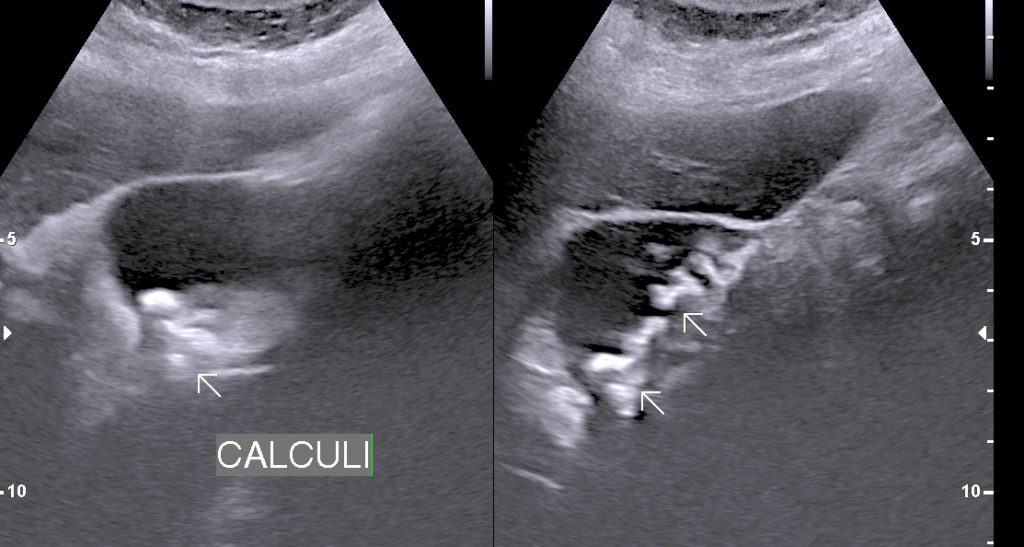

• Multiple Calculi

• Cholecystitis: Cholecystitis is Inflammation of gall bladder. Acute calculus cholecystitis results when calculus/calculi get impacted at neck of gall bladder or cystic duct.

• Finding: Sonography shows thickened oedmatous walls of gall bladder & impacted calculi. Sludge, pericholicystic fluid , localized abscess are additional findings. Sometimes gall bladder is so overdistended that impacted calculi may not be visualized.